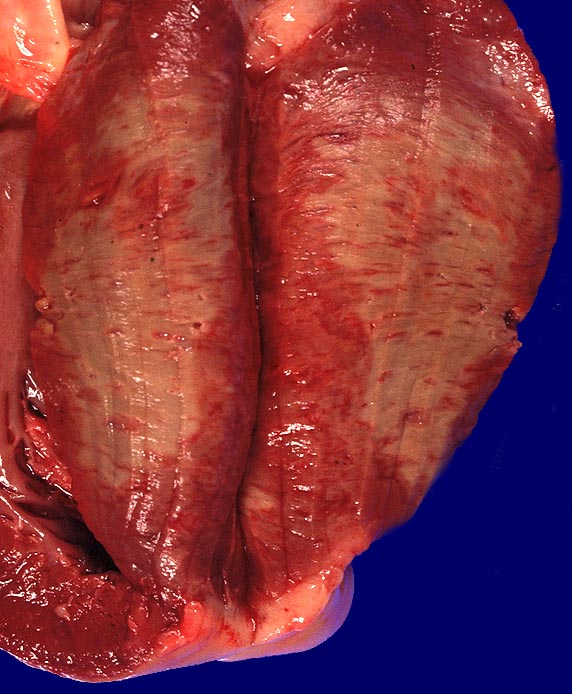

Der klassische Infarkt ist anämisch und ist innerhalb der ersten 15 Stunden als Myokardabblassung ( 335)

später als erhabene lehmgelbe Nekrose mit schmalem hämorrhagischem Randsaum erkennbar. Nach thrombolytischer Therapie können durch Reperfusion der ischämisch geschädigten terminalen Strombahn auch hämorrhagische Infarkte auftreten. Lokalisation und Größe des Myokardinfarktes hängen von verschiedenen Faktoren ab: Lokalisation und Ausmaß der Koronarveränderungen, Größe des vom betroffenen Gefäß versorgten Myokardareals, Sauerstoffbedarf des schlecht perfundierten Myokards, Vorhandensein von Kollateralen und Vorhandensein von Koronarspasmen.

Das Präparat stammt von einer 90 jährigen Patientin. Makroskopie: schwere stenosierende Koronarsklerose mit frischem thrombotischem Verschluss des Ramus interventricularis anterior der linken Koronararterie. 8x9cm grosser akuter transmuraler anteroseptaler Myokardinfarkt.